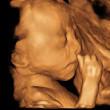

今天21周+3天去照了四维彩超特别想早知道男女,具体数据如下:双顶径50mm,头围188mm,腹围162mm,股骨长36mm,肱骨长35mm,小脑横径17mm,胎儿体重413G,羊水暗区最大深度约52mm,胎心率158/min,心率齐,脐带血流RI0.61,A/B2.56,胎盘附子宫后壁,厚22mm,胎盘0级,哪位高手知道的请告诉一下,万分感谢!